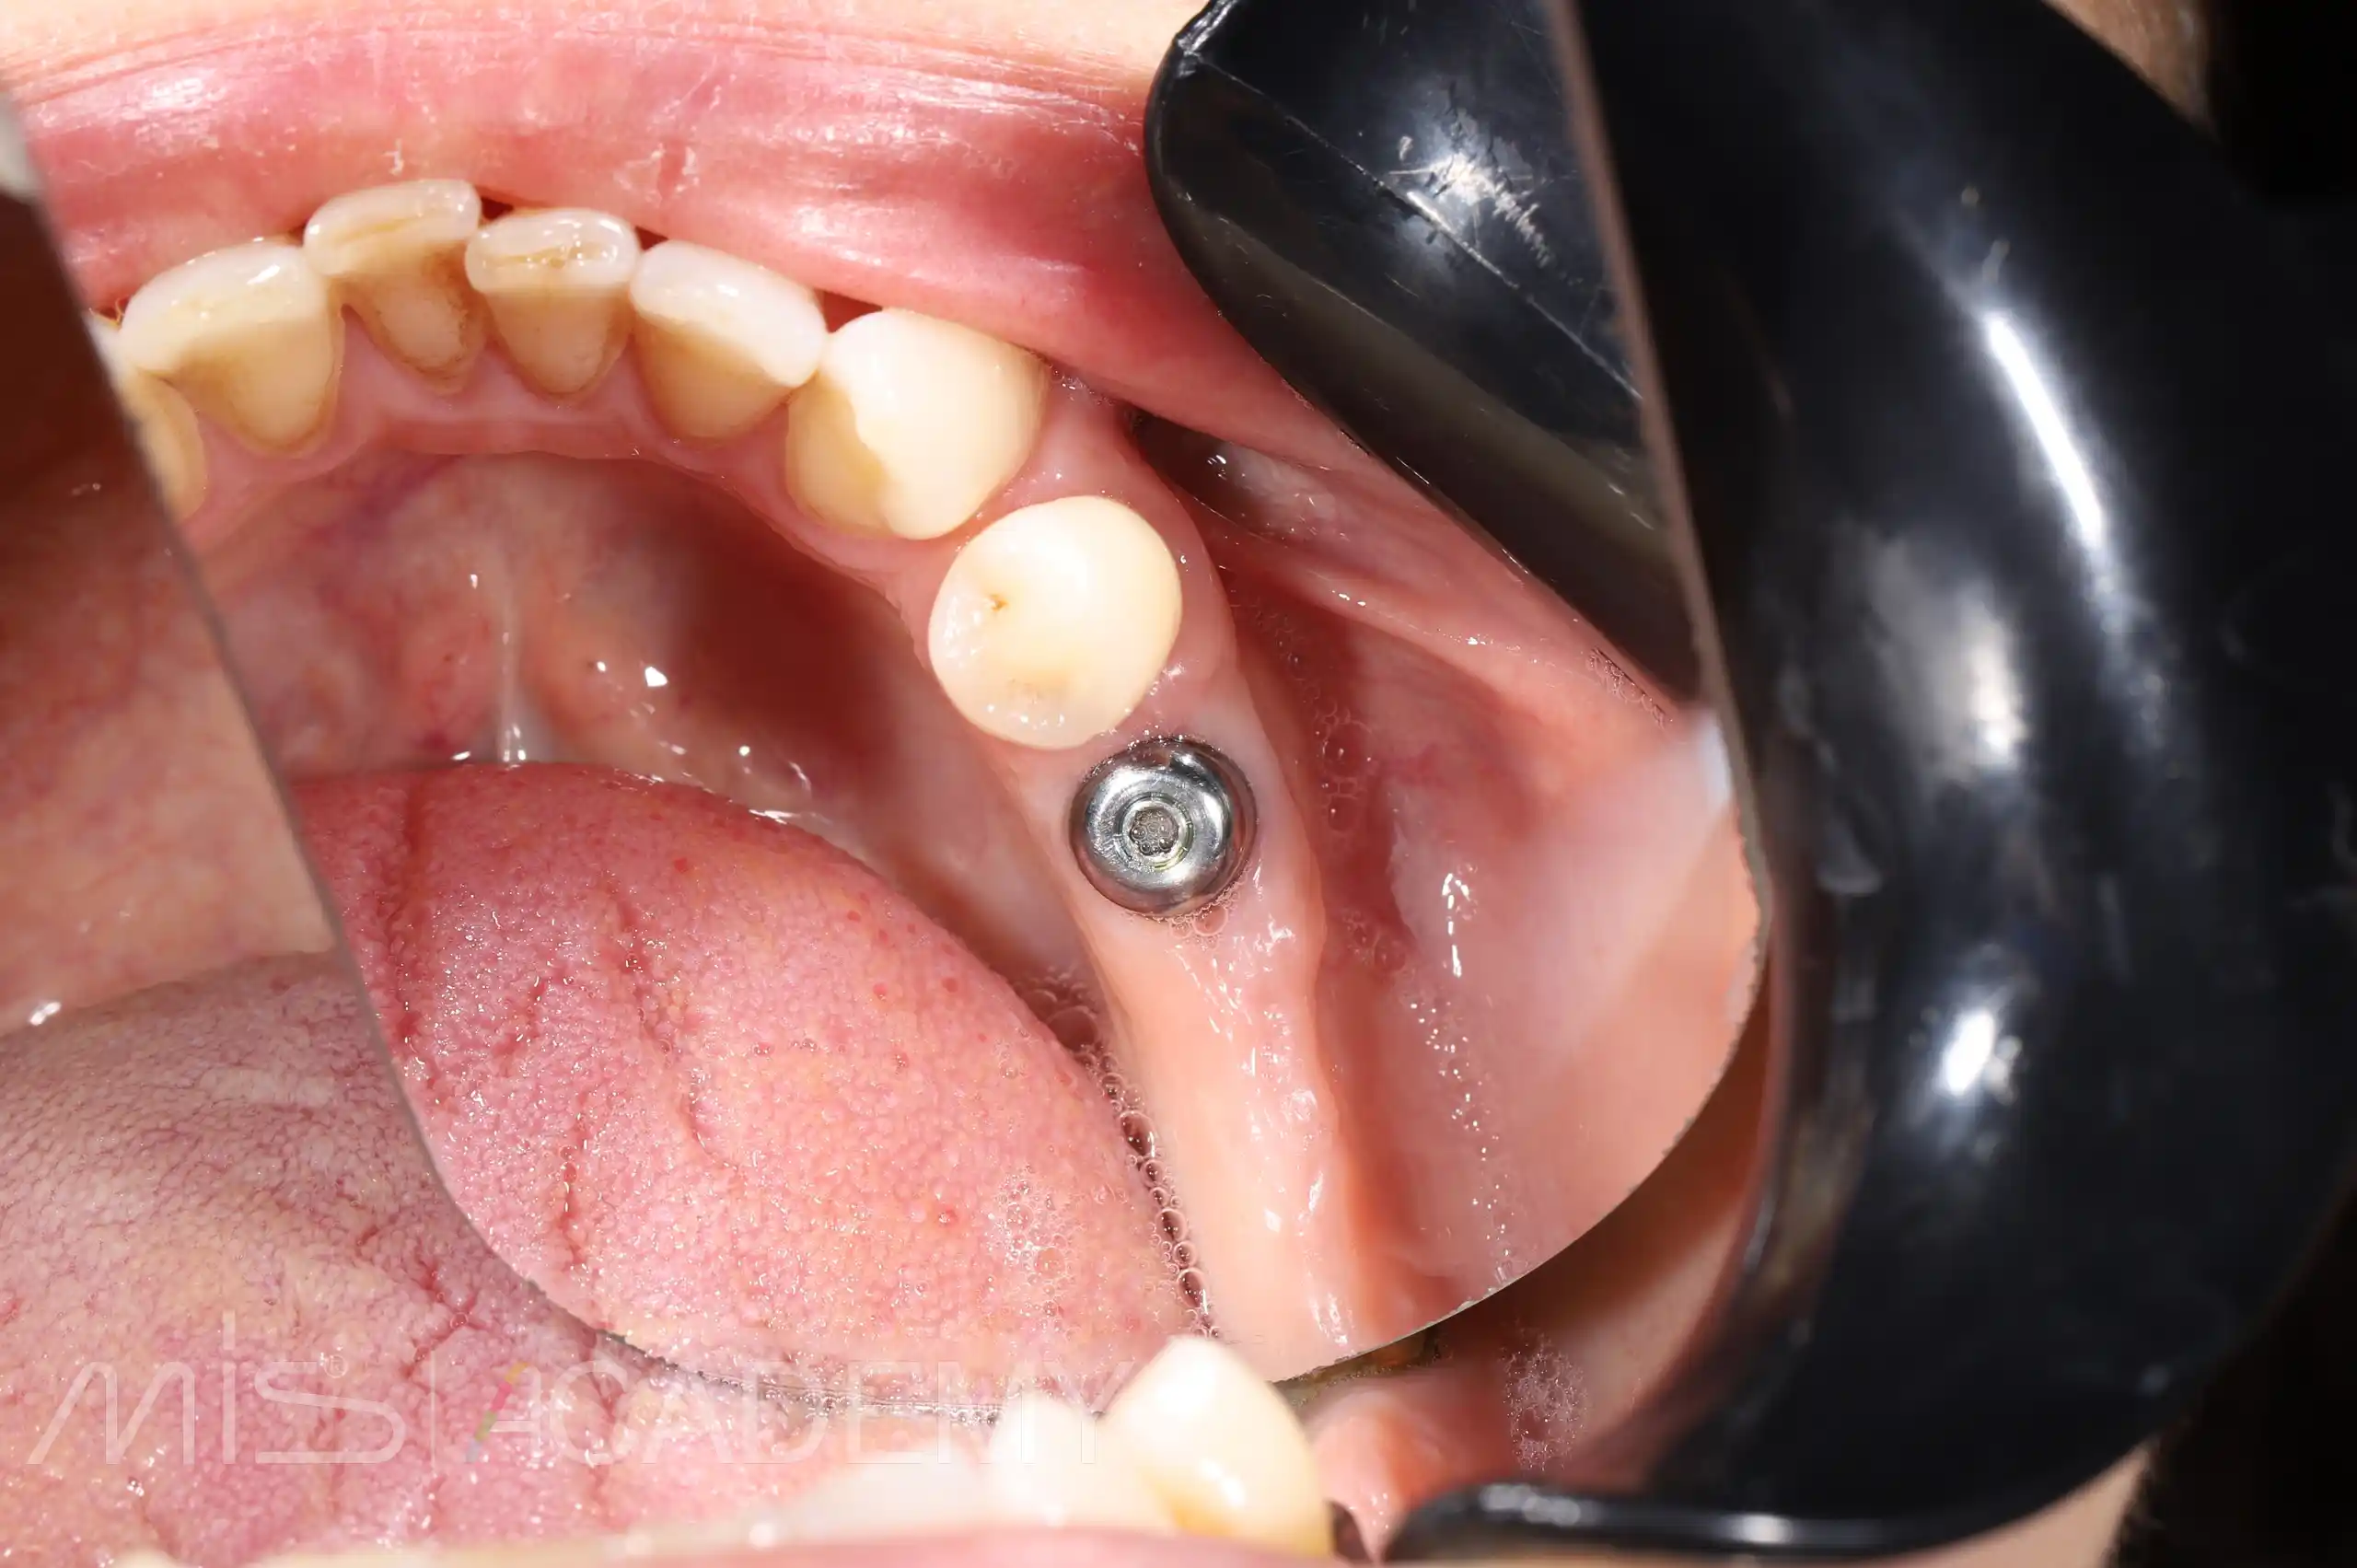

Установка имплантатов MIS C1 в области 46, 35, и 37 по навигации.

— МЮ абатменты в 3 сегменте.

— ССТ, были добавлены методики Poncho.